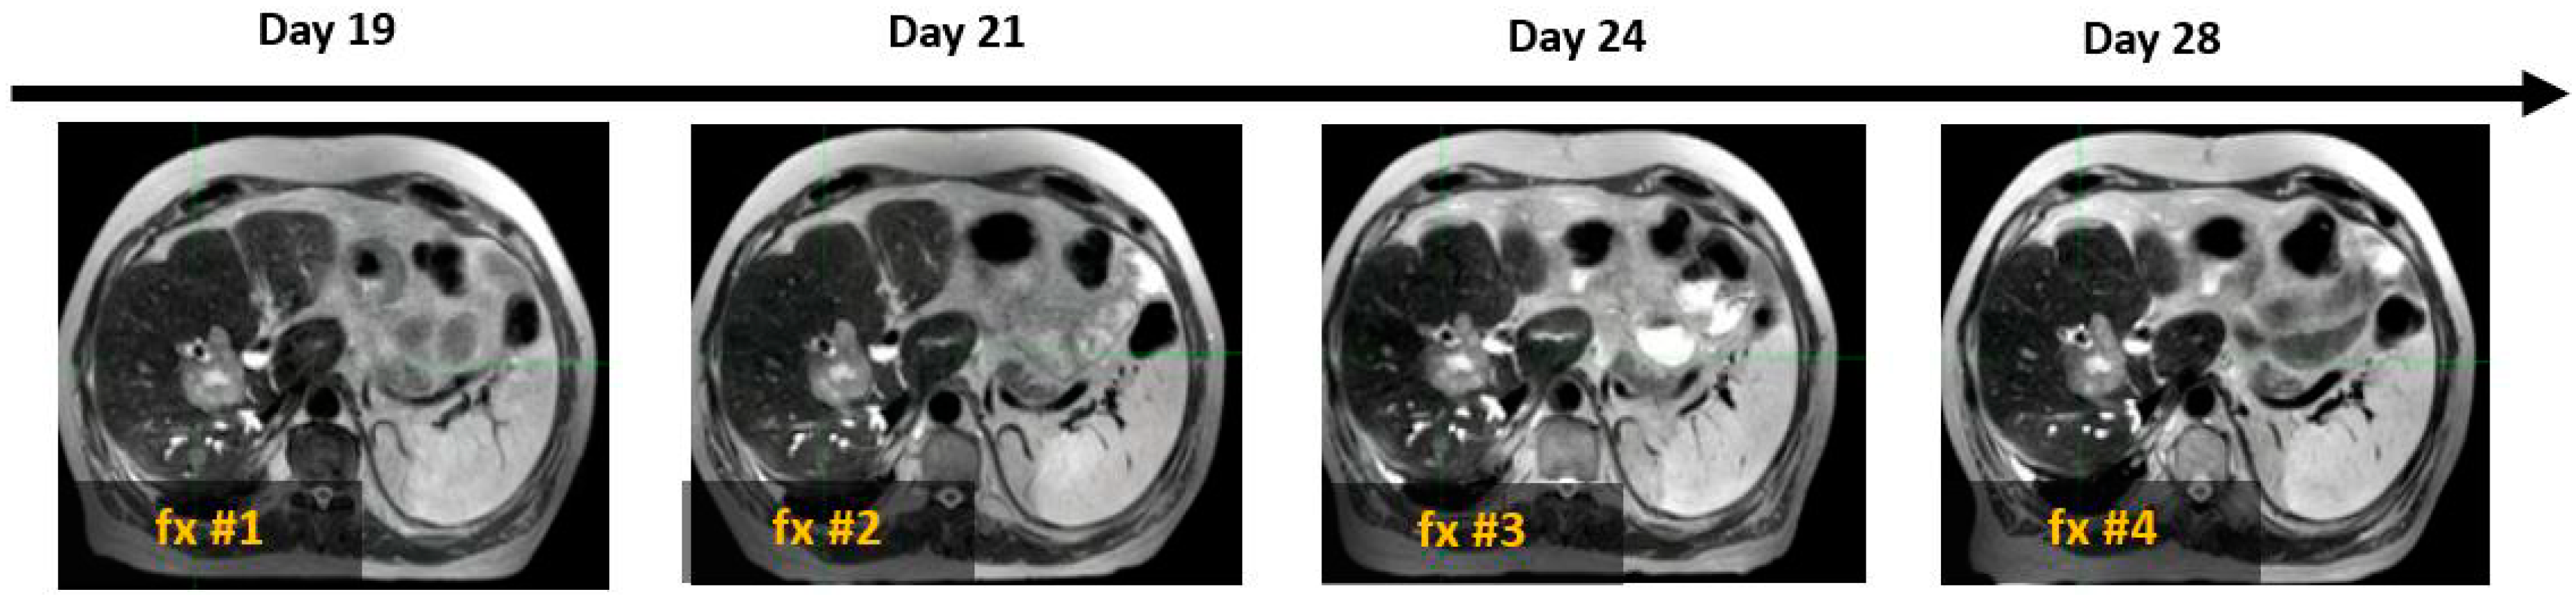

Figure 6 presents the SPION-enhanced MR imaging of FLV in three patients: (A) patient with small colon cancer liver metastasis, with normal liver function and morphology; (B) patient with colon cancer liver metastasis and history of prior hepatectomy, radiofrequency ablation, and prior liver SBRT; and (C) patient with Child–Pugh B cirrhosis and prior SBRT to hepatic segments 2 and 8, performed a year before reirradiation with current SBRT. In the noncirrhotic patient (A), SPION distribution across the liver parenchyma was diffuse and homogeneous, with T2W imaging showing FLV closely matching the liver volume on the non-contrast MRI scan and the predicted individual liver volume. In the second patient (B) with an intrahepatic recurrence of colon cancer metastasis, FLV closely matched the individual predicted liver volume, despite the hypertrophy of healthy liver parenchyma due to prior liver-directed therapies. In contrast, patient (C) with advanced cirrhosis and prior liver-directed therapy showed a marked sequestration and retraction of FLV in the SPION-MRI. As a result, the residual FLV was significantly smaller than the anatomic liver volume from non-contrast MRI, representing only 40% of the predicted liver volume.

Figure 6. Automated contouring of functional (yellow) and anatomic (blue) liver volumes in three patients: (A) patient with solitary liver metastasis and normal liver function, (B) patient with solitary hepatic metastasis and prior liver-directed therapies, and (C) patient with HCC, Child–Pugh B cirrhosis, and prior SBRT (C). Tumors are marked with arrows.